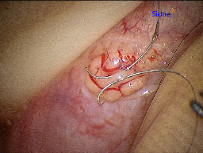

Epididymovasostomy

Epididymovasostomy is required during vasectomy reversal when there is absent sperm in the vas deferens. This signifies that a secondary epididymal obstruction has developed upstream from the vasectomy site. This situation is encountered in approximately 40% of individuals after a vasectomy. Epididymovasostomy can only be performed using a high powered operating microscope, under general anesthesia, by microsurgeons using the finest suture (10-0 nylon).